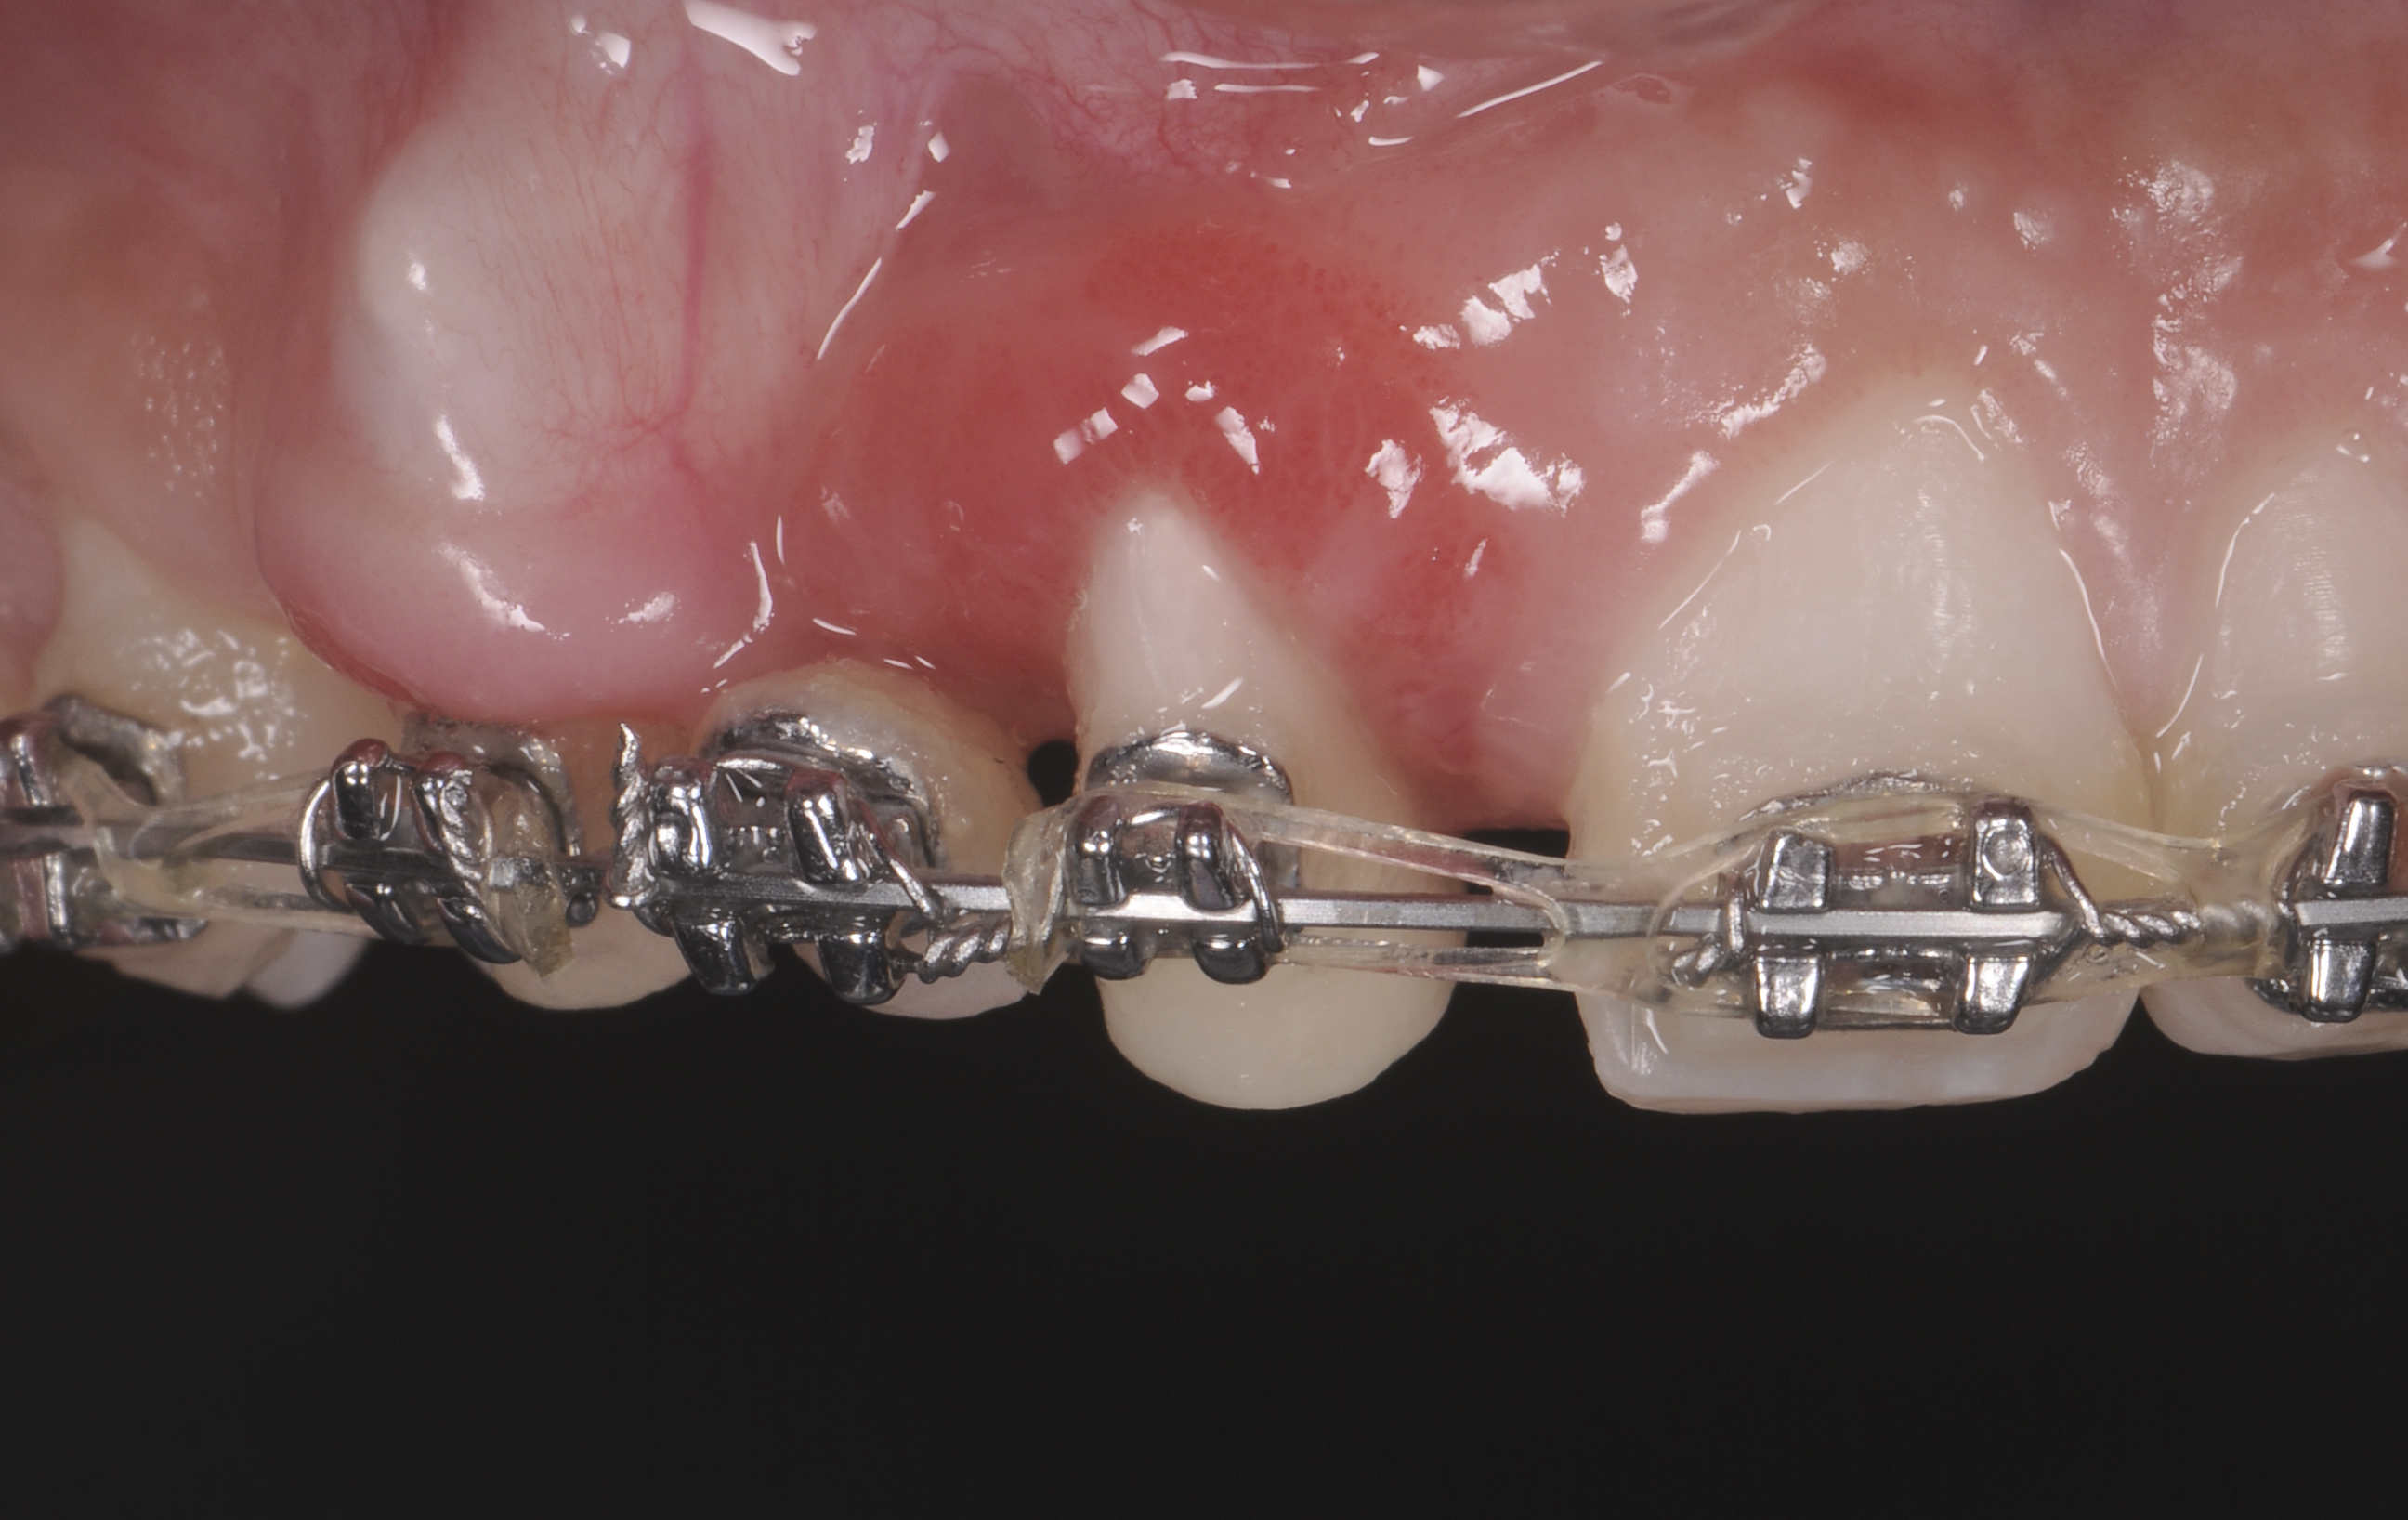

The intraoral examination revealed a substantial deficit of alveolar bone and gingival tissues in the maxillary right lateral incisor area. The ridge defect exhibited vertical and horizontal components, which were associated with a severe loss of clinical attachment on both the mesial aspect of tooth No. 6 and the distal aspect of tooth No. 8. Although probing depths were within normal limits, minimal keratinized gingiva was present and the soft tissues were acutely inflamed. Plaque removal was difficult because of the soft-tissue defect, gingival-margin location, and irregular soft-tissue architecture. Additionally, bone sequestration could be observed through the labial mucosa (Figure 2).